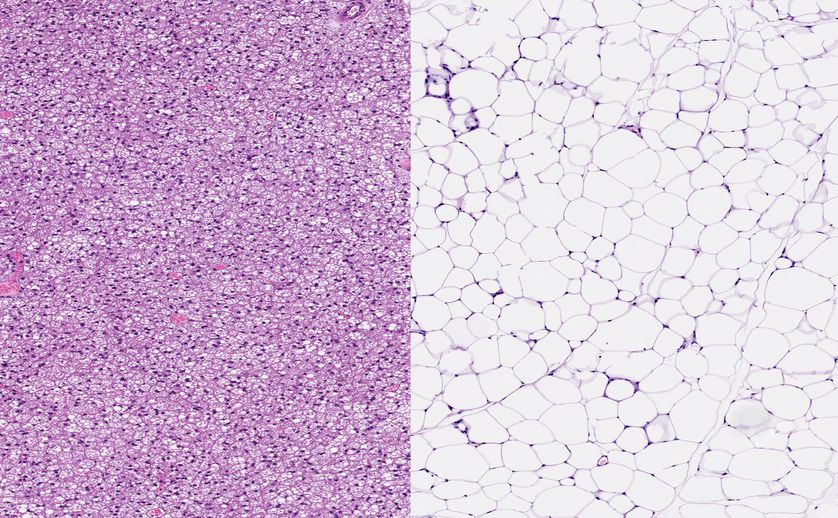

Normal healthy brown fat cells (left) and normal healthy white fat. (Photo: vetpathologist/Shutterstock)

If you can convert white fat (shown above right) to brown fat (on the left), you essentially change a storage area into a burning furnace.

如果您可以將白色脂肪(如右上方所示)轉(zhuǎn)換為棕色脂肪(如左上方所示),那么您實(shí)際上就將一個(gè)存儲(chǔ)區(qū)域變成了一個(gè)燃燒的爐子。